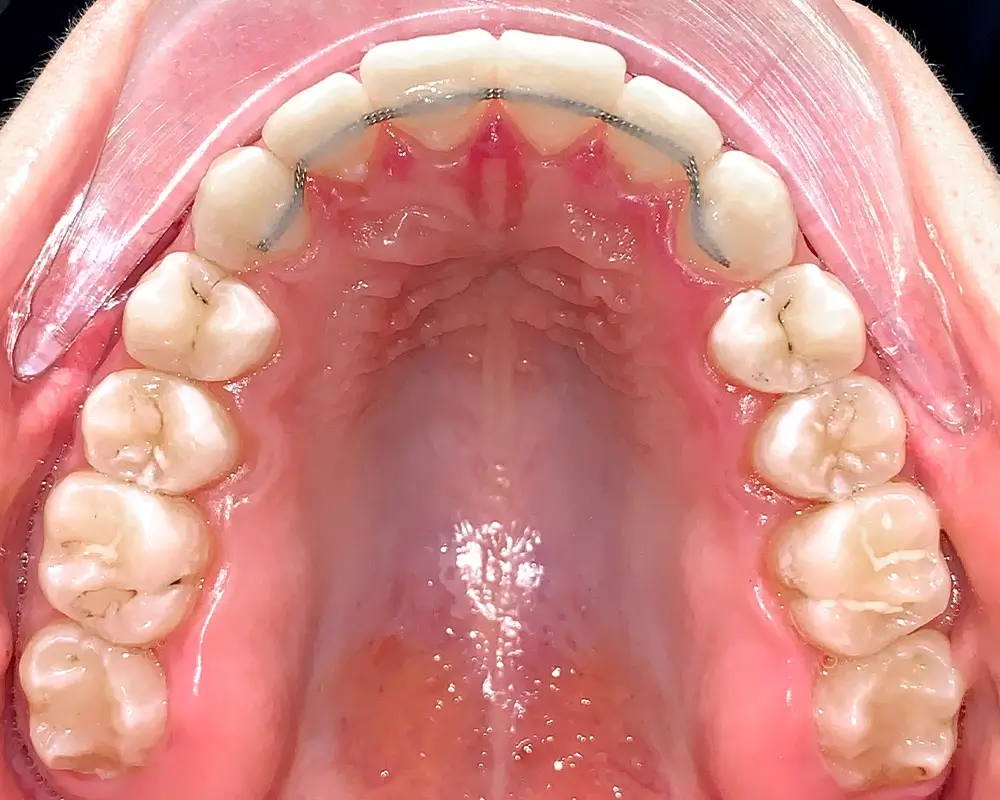

Скученность - Кейс 16

Эффективность устранения дефекта прикуса посредством элайнеров FlexiLigner.

20

Количество кап НЧ

Количество кап ВЧ

Результаты лечения